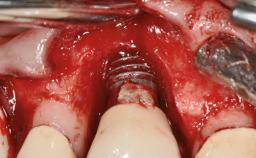

# of Implants 5

Type of Implants Two-Piece

Defining Characteristics Fully edentulous lower jaw to be rehabilitated with two or more implants

Modality > 4 implants, extending to mental nerve region

Bone Volume Horizontally and vertically sufficient